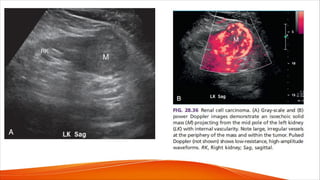

• Solid masses such as renal cell carcinoma or oncocytomas may

demonstrate significant neovascularity that is distinct from vascular

disorders such as pseudoaneurysm or AVM. For example, patients with

oncocytoma can reveal a characteristic spoke-wheel pattern of blood flow

within the tumor (Fig. 28.35).

• Increased neovascularity is also commonly seen in renal cell carcinoma

(Fig.28.36). Color and pulsed Doppler evaluation are helpful in the

characterization of indeterminate renal lesions identified on other

modalities.

• Waveforms obtained from malignant tumors usually show a high-velocity,

low-resistance pattern with velocities significantly higher than normally

seen in renal arteries.